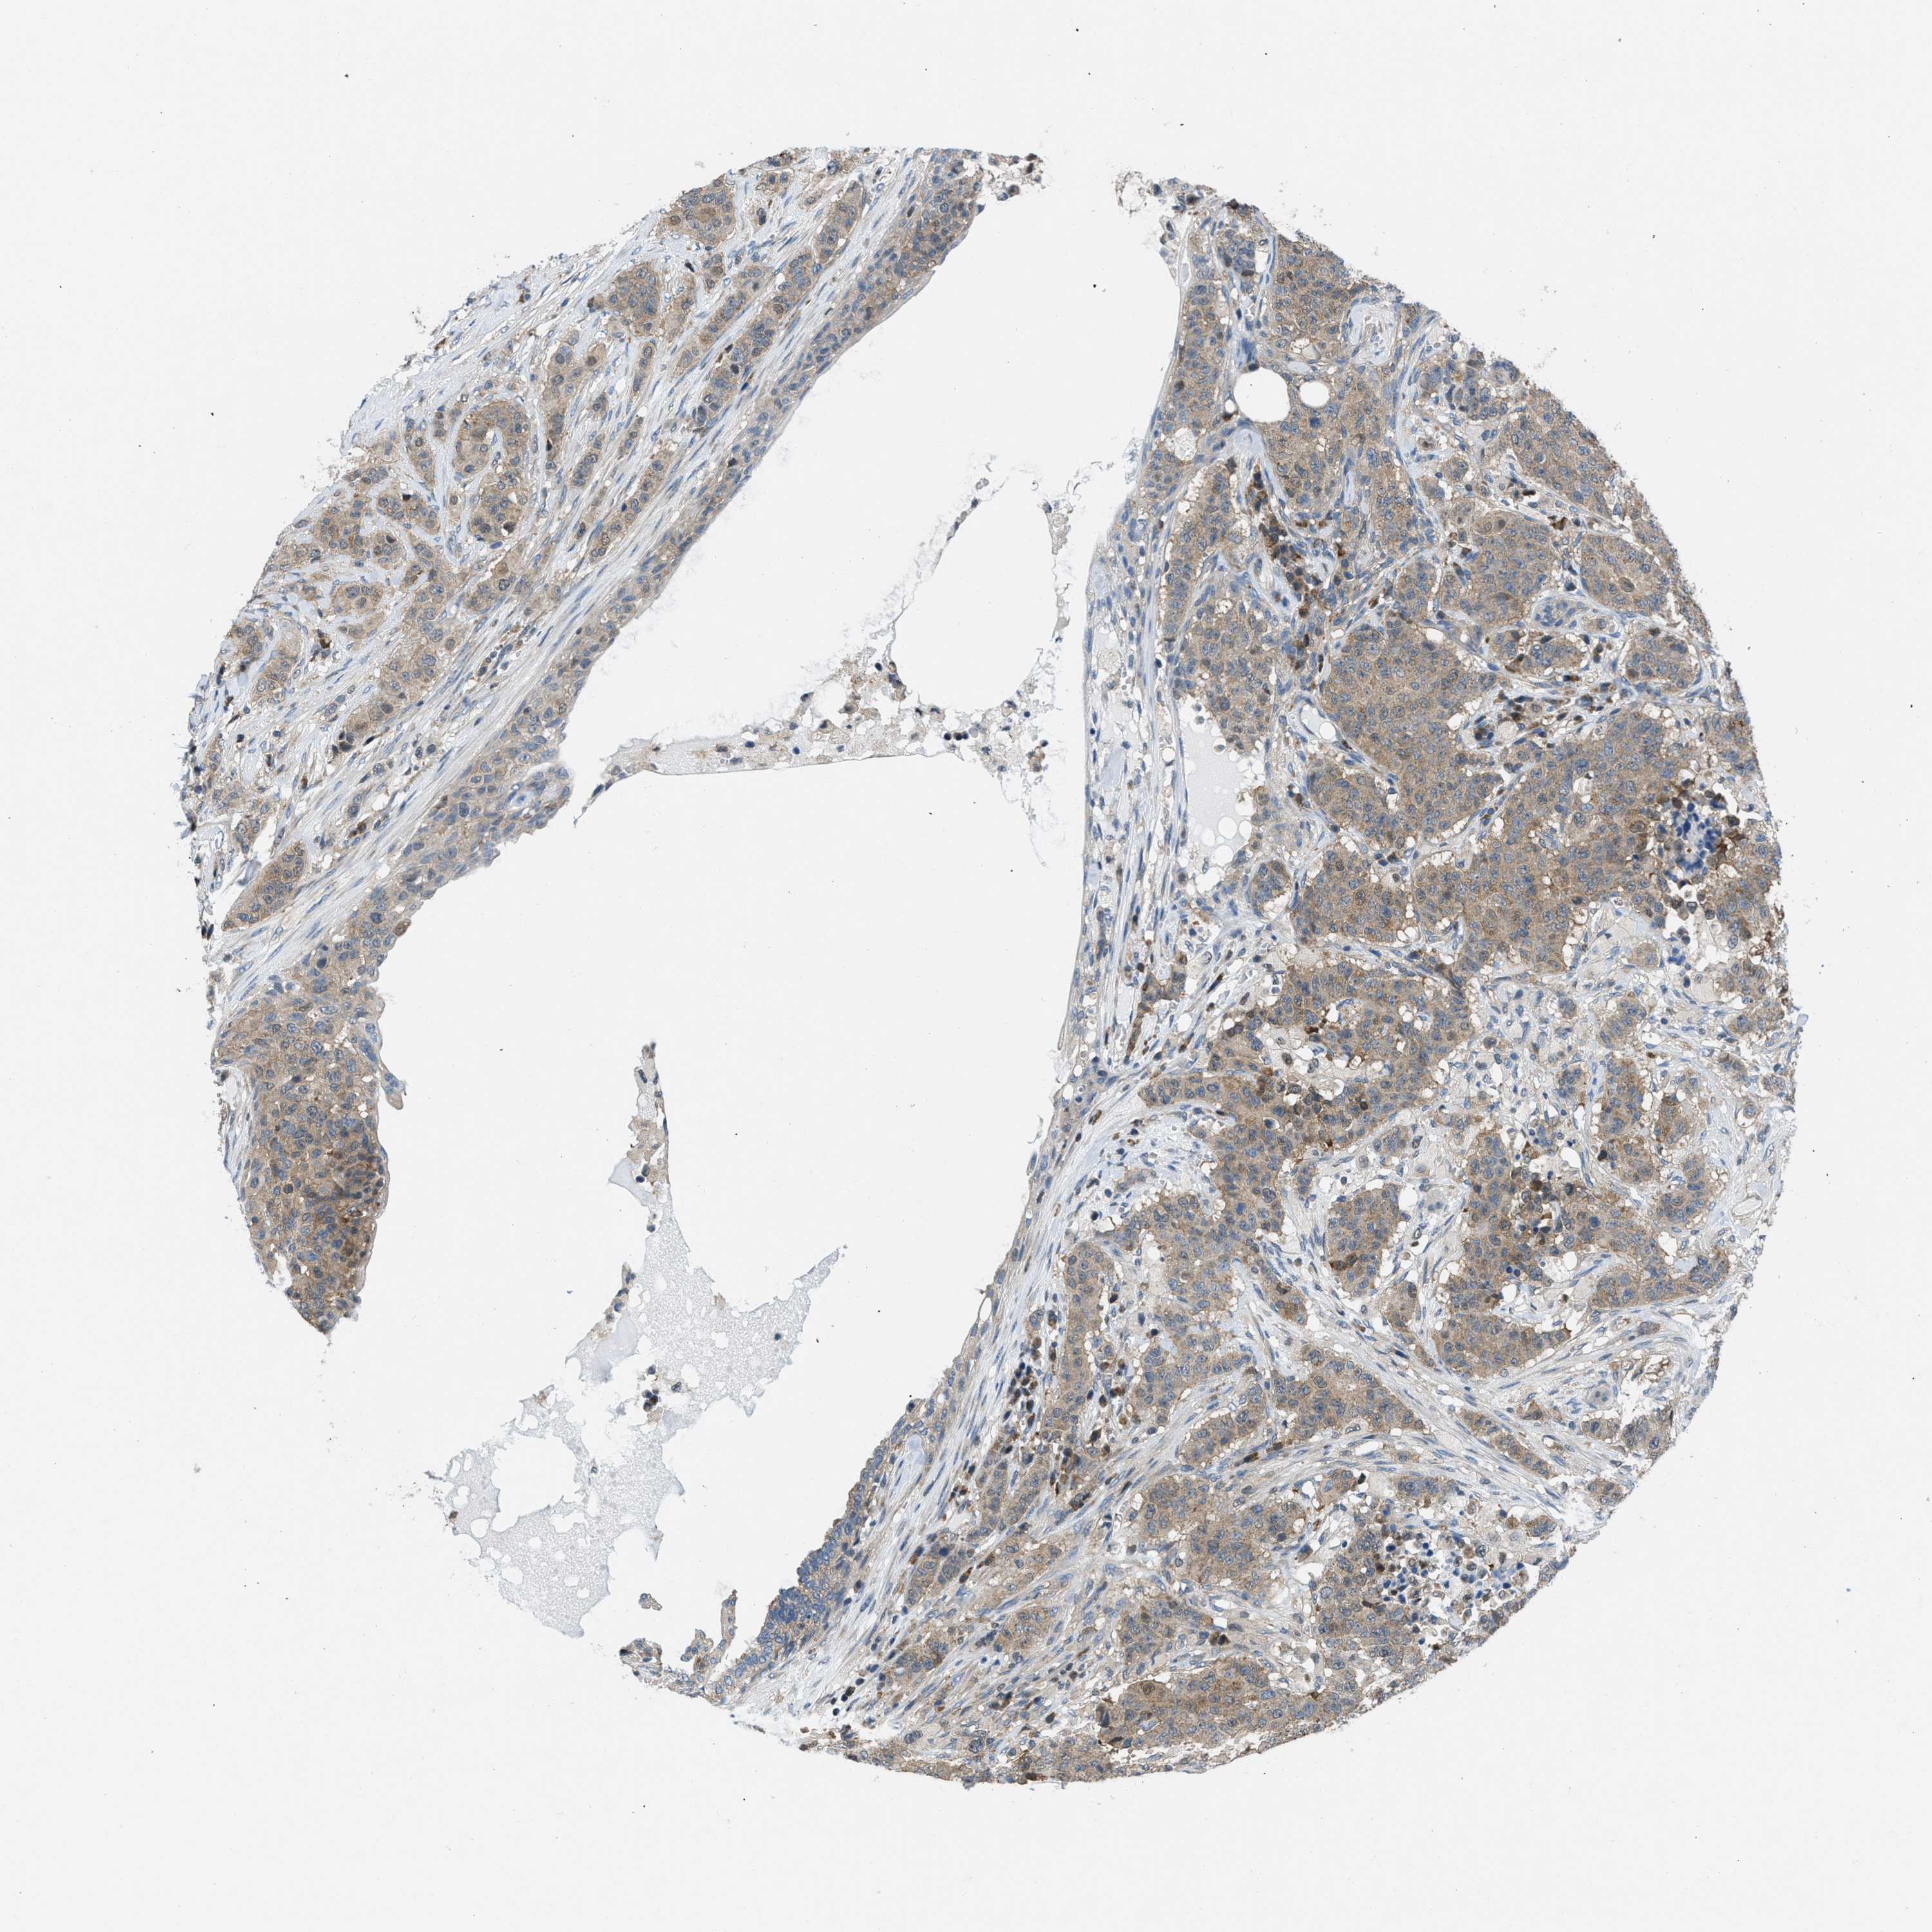

CANCER BREAST CANCER Show tissue menu

BRCA TCGA BRCA VALIDATION PROTEIN EXPRESSION